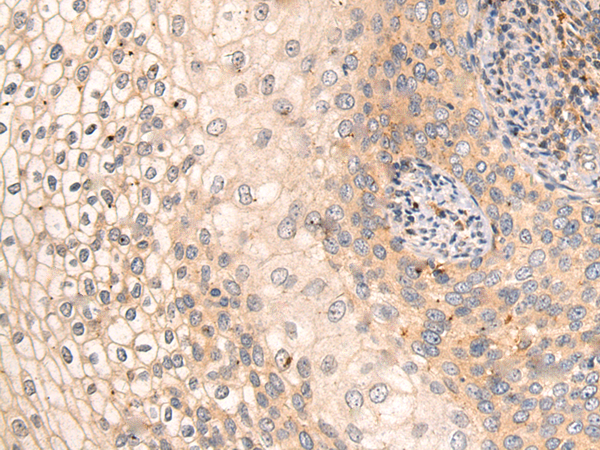

IHC positive control:

Human thyroid cancer and Human liver cancer

IHC Recommend dilution:

15-50